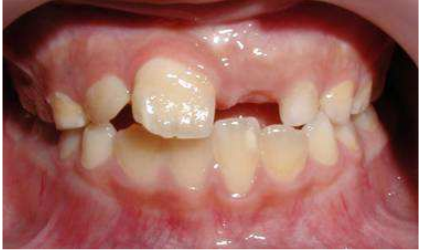

19. 此圖片為十三歲男性矯正患者之口內右邊頰側照片及側面測顱放射線片,請問下列何者是最適切的咬合異常診斷?

(A)Angle Class I with anterior open bite (B)Angle Class II with anterior open bite (C)Angle Class I with anterior crossbite (D)Angle Class II with anterior crossbite